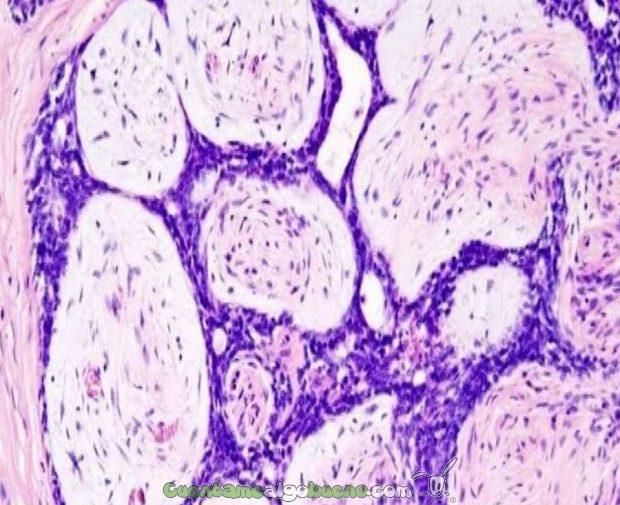

Un grupo de científicos de Estados Unidos ha descubierto un posible fármaco que consigue que las células cancerígenas se autodestruyan.

El estudio, que ha sido publicado en la revista Proceedings of The National Academy of Sciences (PNAS), indica que el compuesto químico activa un mecanismo por el cual las células cancerígenas «se matan a sí mismas» de forma «programada», puntualiza el profesor Matthew Disney, que ha liderado el equipo de investigación.